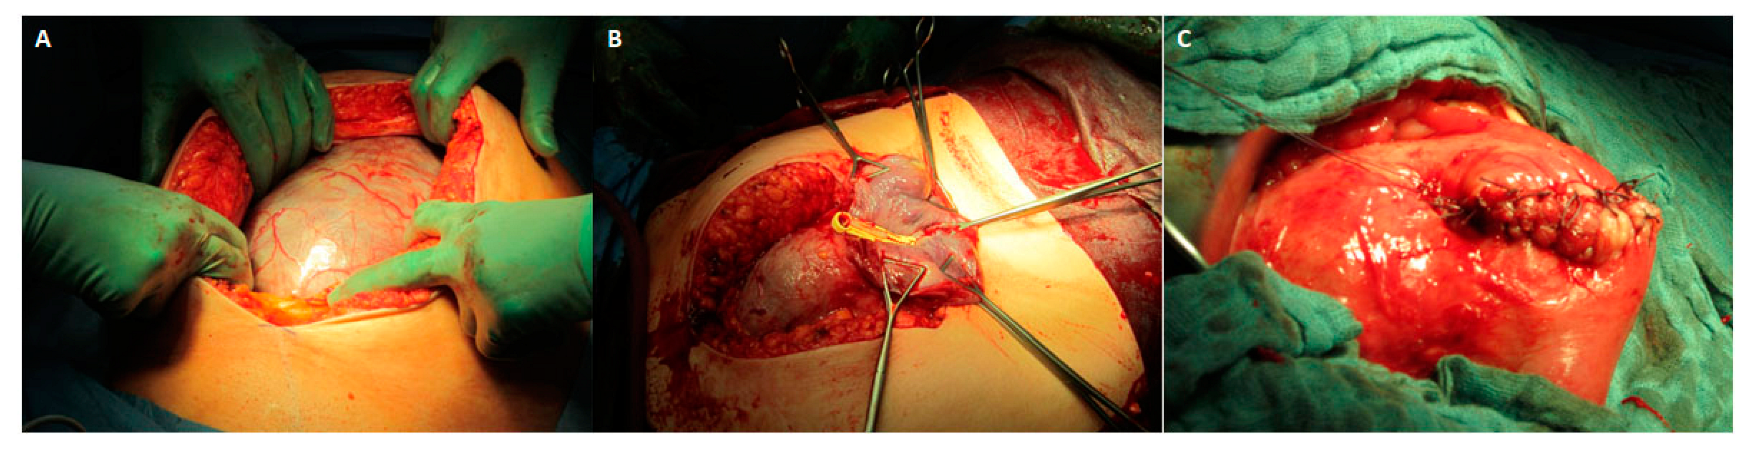

Treatment options (leaving the placenta in situ, partial excision of invasive placental areas, and CS-HE) were discussed in detail with the patients before making an informed decision about further management. Surgery was performed by a team of senior obstetricians and anesthetists with neonatologic stand-by, mainly under general anesthesia. The placenta was avoided by a uterine fundal transverse or longitudinal incision after abdominal access by supraumbilical or lower midline incision (Figure 2) [39]. An intraoperative ultrasound was performed at the surgeon’s discretion to locate the placenta. Uterotonic agents were not administered [40].

Figure 2.

(A): A large area of PAS is seen on the front wall of the uterus after abdominal access by a supraumbilical midline incision. (B) Uterine fundal longitudinal incision on the back wall of the uterus avoiding the placenta. (C) Closed uterotomy after leaving the placenta in situ.